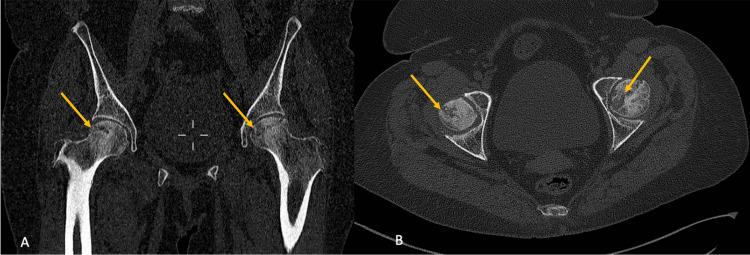

SARS‑CoV‑2 infection remains a hot topic; it is characterized by its multi-systemic involvement. Corticosteroid intake has been the subject of worldwide attention as a potentially effective treatment against coronavirus disease 2019 (COVID-19). Corticosteroids are registered on the WHO list of essential medicines, easily accessible for a low price, and particularly useful for different categories of people. The authors highlight the impact of corticosteroid administration for COVID-19 treatment on the occurrence of aseptic osteonecrosis in the femoral head. They also examine the pace of onset in comparison to corticosteroid usage unrelated to COVID-19. This article presents a patient with osteonecrosis of the femoral head after taking corticosteroid therapy in the treatment of COVID-19. The dose taken by the patient is 90 mg of dexamethasone equivalent to 600 mg of prednisone. The patient experienced the onset of OTA, and the duration of development was three months, indicating a relatively brief period. Comparison was made with data from the literature from 6 months to 1 year after taking corticosteroids in a context outside of COVID-19.

严重急性呼吸综合征冠状病毒2型(SARS-CoV-2)感染仍是一个热门话题;其特点是多系统受累。作为一种针对2019冠状病毒病(COVID-19)的潜在有效治疗方法,服用皮质类固醇一直是全球关注的焦点。皮质类固醇被列入世界卫生组织基本药物清单,价格低廉且易于获取,对不同人群尤其有用。作者强调了COVID-19治疗中使用皮质类固醇对股骨头无菌性骨坏死发生的影响。他们还与与COVID-19无关的皮质类固醇使用情况相比,研究了发病速度。本文介绍了一名在COVID-19治疗中接受皮质类固醇治疗后发生股骨头坏死的患者。患者服用的剂量为90毫克地塞米松,相当于600毫克泼尼松。患者出现了骨坏死(OTA),发展持续时间为三个月,表明时间相对较短。与COVID-19以外情况下服用皮质类固醇后6个月至1年的文献数据进行了比较。